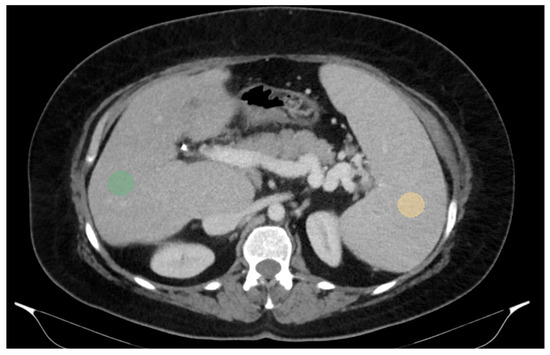

For two-dimensional (2D) segmentation, regions of interest (ROIs) were manually delineated on the portal-venous-phase images. In the liver, ROIs were placed in the right lobe, at the level of 9th to 10th intercostal space, approximately 10 mm below the liver capsule and avoiding large vessels, which is also the typical site for liver biopsy and VCTE. Spleen ROIs were similarly delineated while avoiding major vascular structures (Figure 1).

Figure 1.

Abdominal portal-venous-phase CT scan, axial plane. Example of 2D liver and spleen segmentations. Two-dimensional liver and spleen segmentations were obtained by placing regions of interest (ROIs) in the right liver lobe at the level of the 9th right intercostal space (green ROI) and in the spleen (orange ROI), while avoiding major vascular structures.